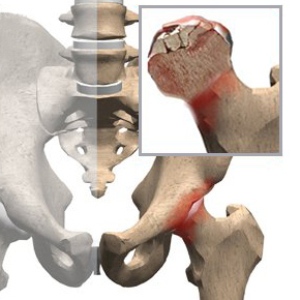

Остеонекроз – это патологическое состояние, которое характеризуется некрозом участка той или иной кости с развитием лизиса или расплавления, остеоцитов, и образованием участков с некрозом. Остеонекроз может развиться на любой кости, но для этого необходимы определённые условия и причины.

Основная и самая частая причина остеонекроза мыщелка и головки бедренной кости – это травма, особенно в пожилом и старческом возрасте. При этом патология чаще всего отмечается у мужчин, чем у женщин, и более, чем в 60% всех диагностированных случаев остеонекроз может быть двухсторонним.

При этом для развития патологии необходимо наличие перелома со смещением. Если же перелом произошёл без смещения отломков, то в этом случае некроз развивается очень редко. Ещё одна причина – вывих головки бедра. При этом, если он длительное время не будет вправлен, то развитие некроза в этом случае обеспечено практически в 80% всех случаев.

Перелом и вывих могут вызвать остеонекроз и в том случае, когда будет нарушено кровоснабжения мягких тканей и самих костей за счёт переживания сосудов отломками костей, или же смещенной головкой кости.